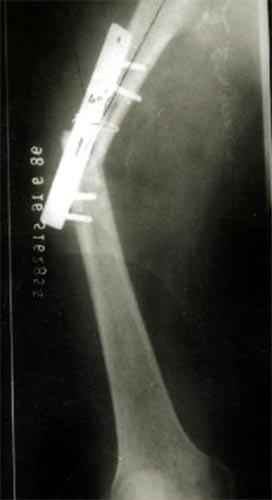

病例四、患者男性,13岁,股骨干中远1/3骨母细胞瘤,切除瘤体后形成大段骨缺损。我们用髓内钉和钢板内固定,大段异体骨植骨,骨生长因子和骨髓细胞的植入,骨缺损在12个月顺利愈合。